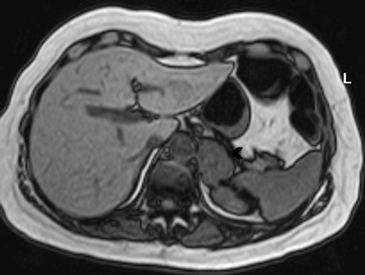

La apariencia en RM es inespecífica, presentando con mayor frecuencia hipointensidad con respecto al parénquima hepático en secuencias T1, hiperintensidad heterogénea en secuencias ponderadas en T2 y ausencia de caída de señal en secuencias fuera de fase, con escaso refuerzo progresivo tras el uso de Gadolinio endovenoso (Figuras 30 a y b).

A

B